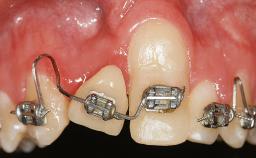

A 30-year-old woman was referred by her general dentist for evaluation of an esthetic complication related to previous implant treatment for congenitally missing maxillary lateral incisors. The patient’s chief complaint was the inadequate esthetic appearance of her smile. The case demonstrates the use of a combined approach to achieve optimal results. Two different flap designs - a tunnel technique and a coronally advanced flap - are employed based on the surgical objectives for the affected site.

Placement Protocol Early or late implant placement